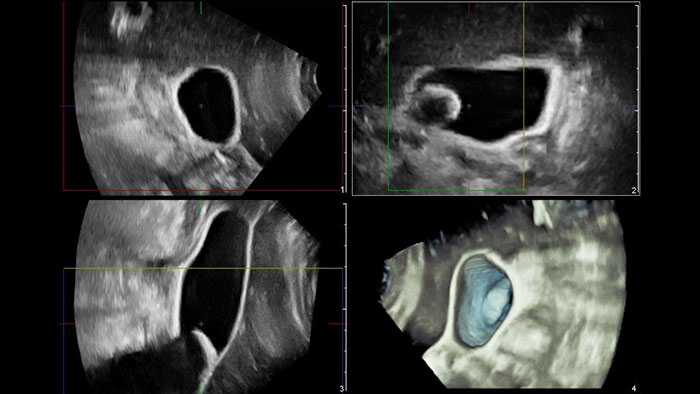

US Q-App General Imaging 3D Quantification (GI3DQ) provides advanced viewing, manipulation, and quantification of 3D data sets. Perform advanced functions such as MPR interrogation, iSlice tomographic imaging, and volume rendering as well as volumetric measurements using multiple methods including semi-automated tools. Results generated from this tool can be appended to the patient’s exam for complete documentation.